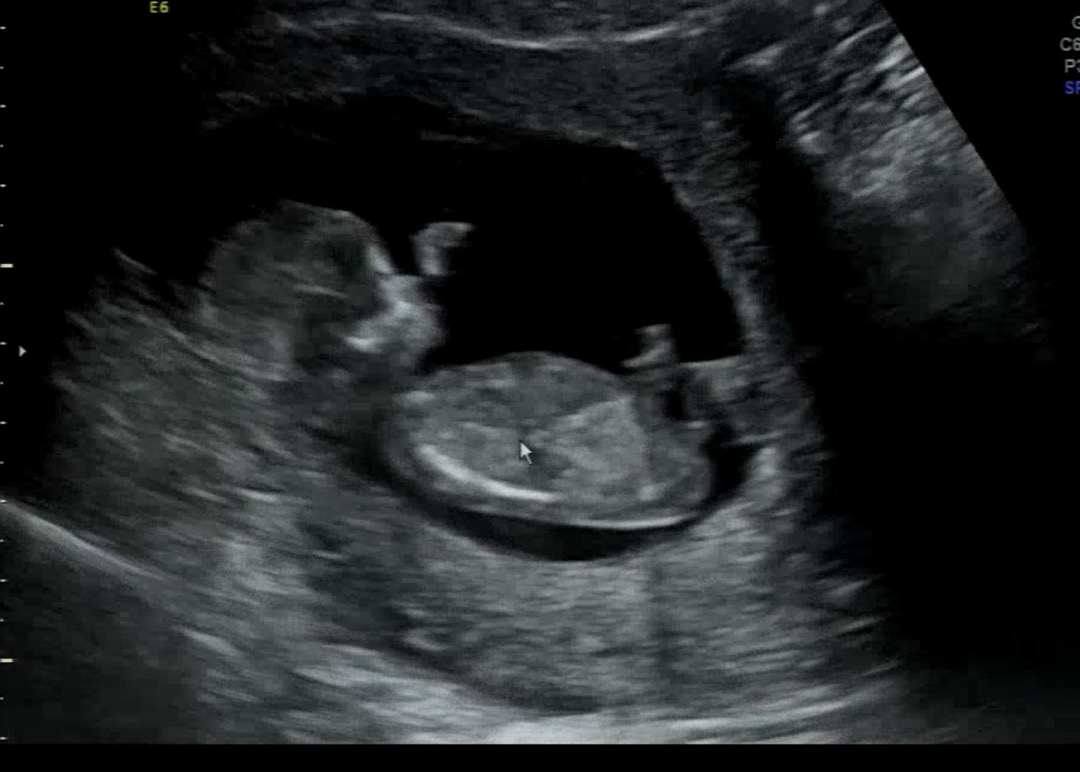

12주 3일입니당!! 각도법 혹시 보일까요???

좀 흐린가요ㅠㅠ 궁금해요:)